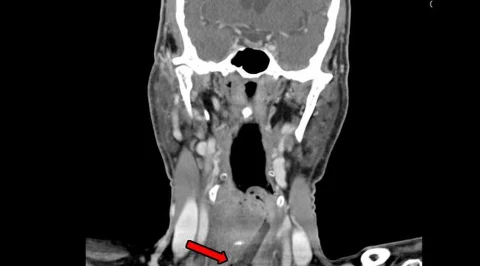

Na zdjęciu MRI mózgu pacjenta (A) i kostki (B). Strzałka na zdjęciu B wskazuje powiększenie ścięgna Achillesa pacjenta, które zwęża się na końcu /Fot. JAMA Neurology

GeekExtra

Najpierw były drobne guzki. Dziesięć lat później okazało się, że to groźna choroba